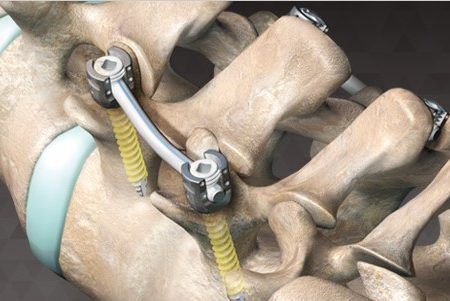

flamenco